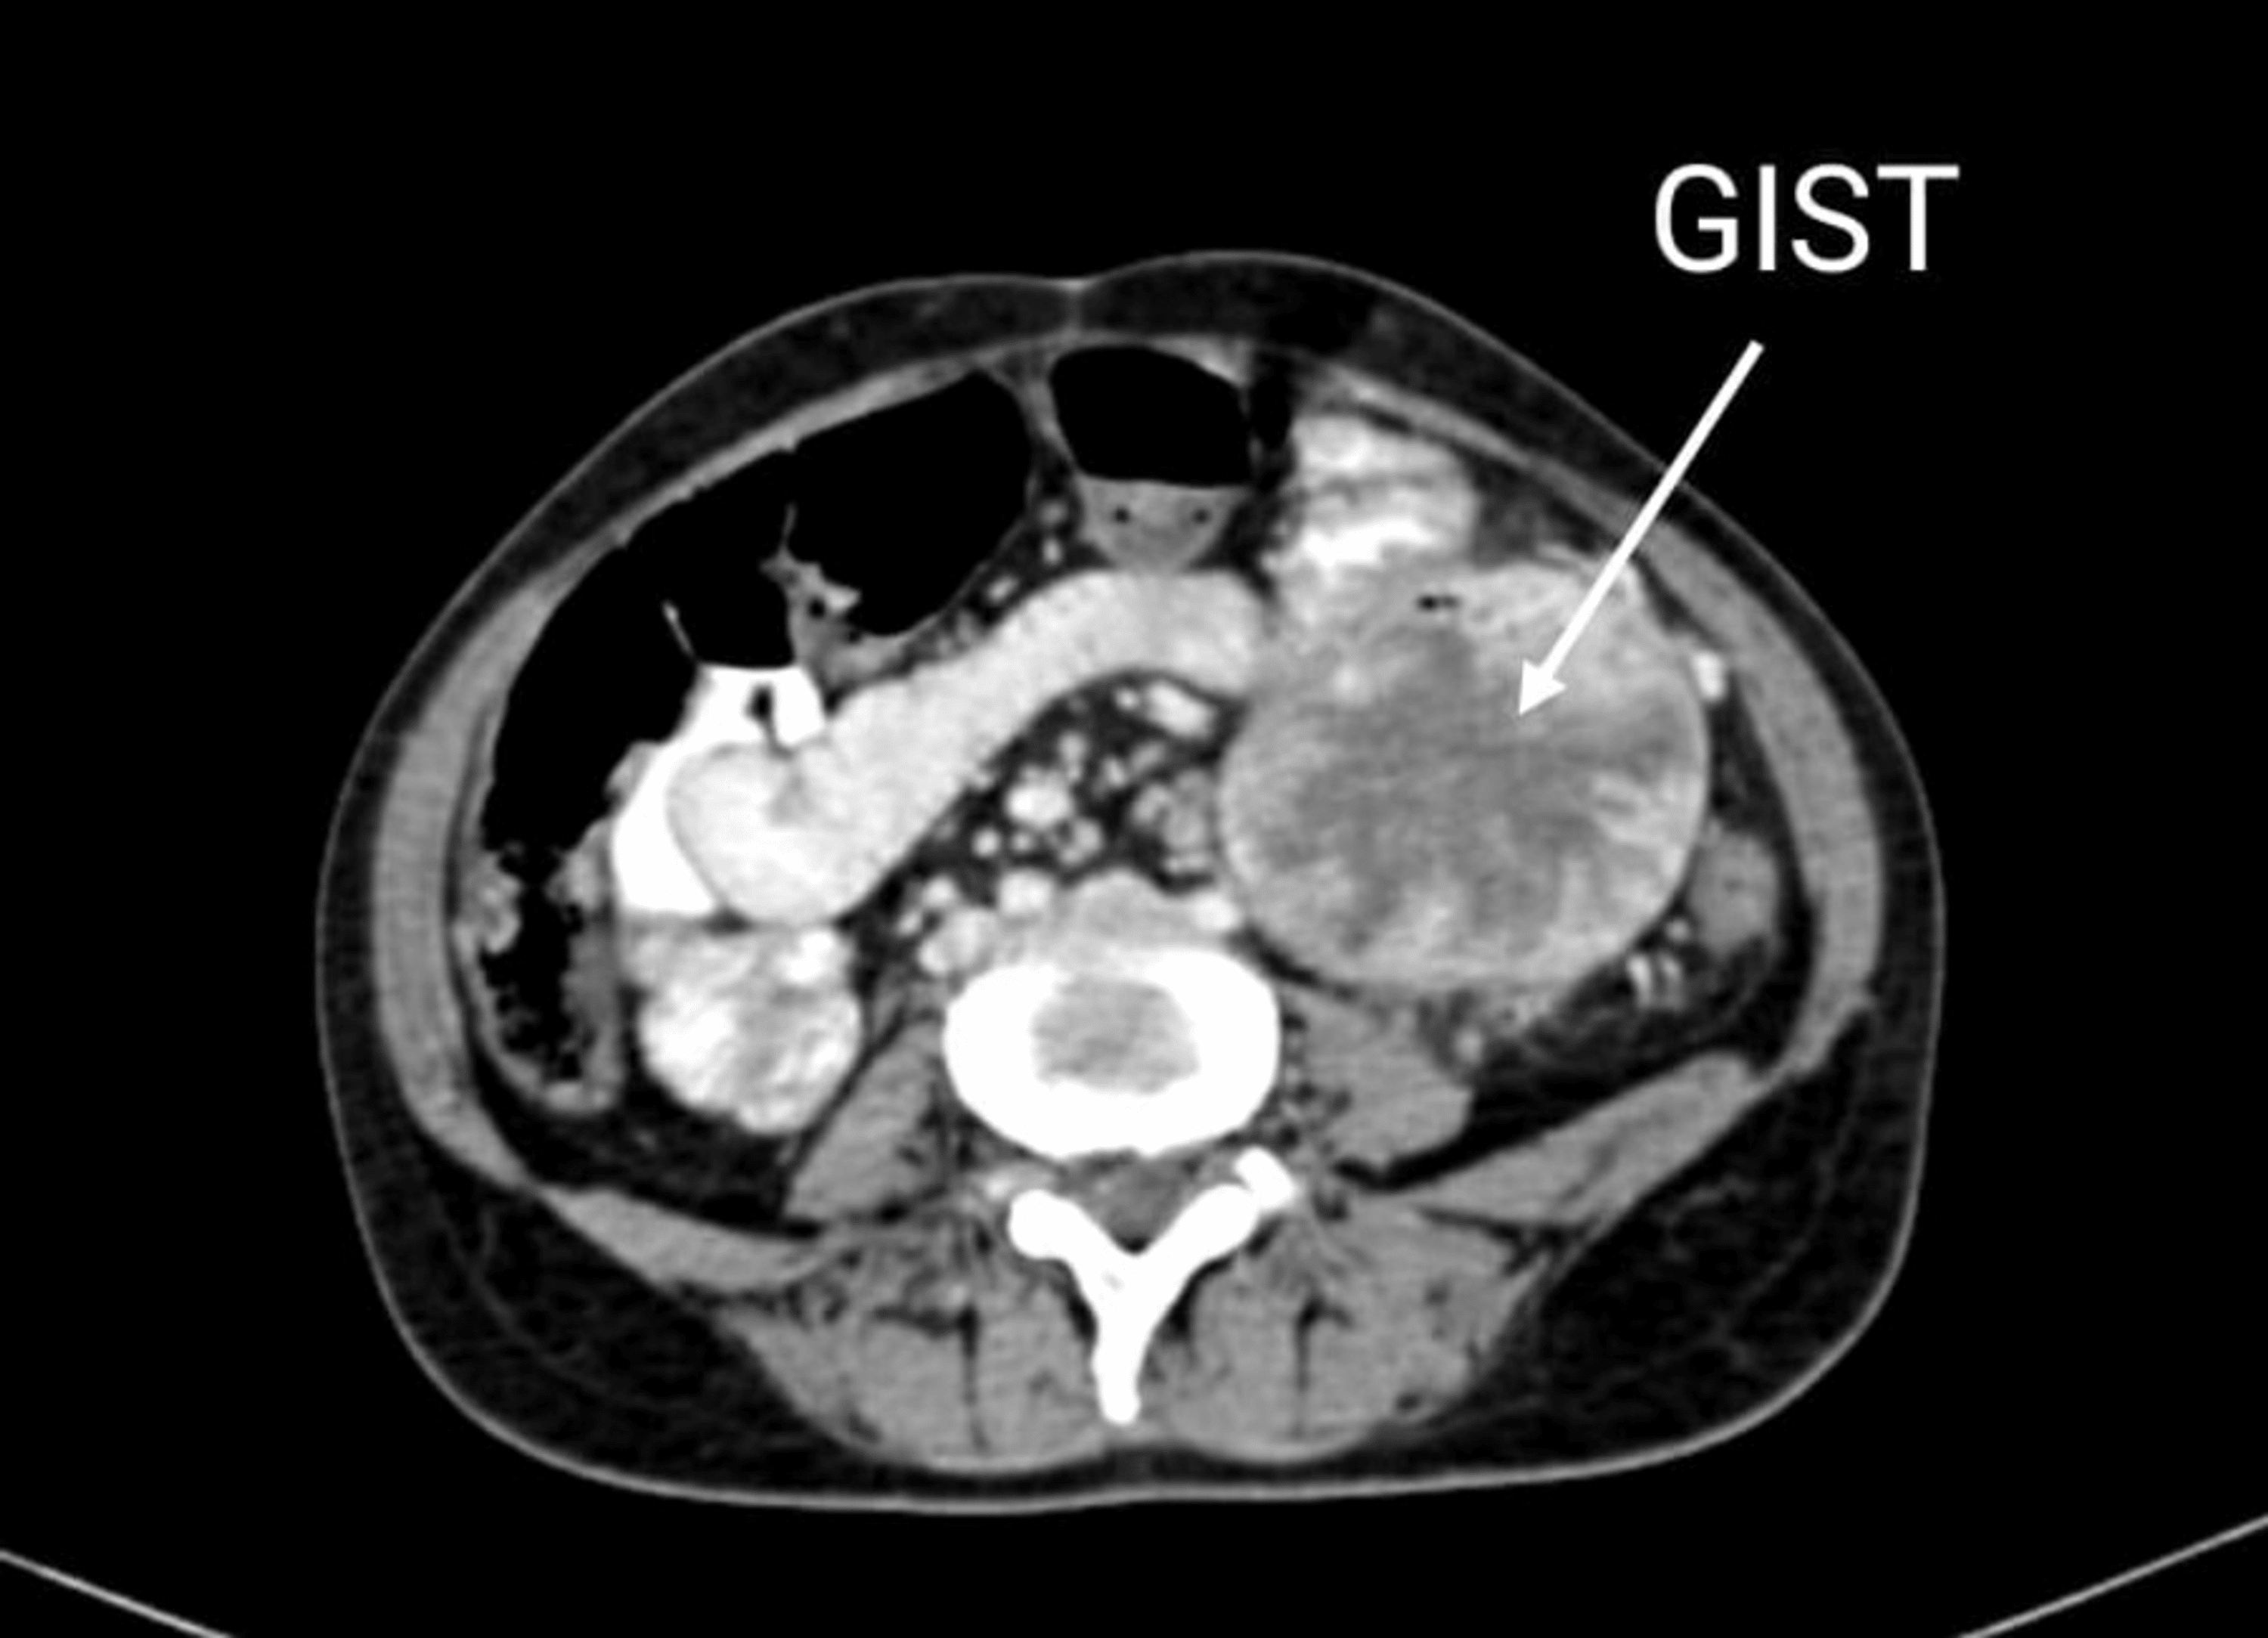

Cureus Coincident Double Tumor of the Breast and Gastrointestinal Concertina Jejunum The jejunum diameter is 4 cm,. Web the aim of this review is to outline the current methods of investigation of the jejunum, and provide a comprehensive review of common pathologies. Web the accordion sign (also known as concertina sign) is seen on ct of the abdomen and refers to the similarity. Web the accordion sign (also known as the. Concertina Jejunum.